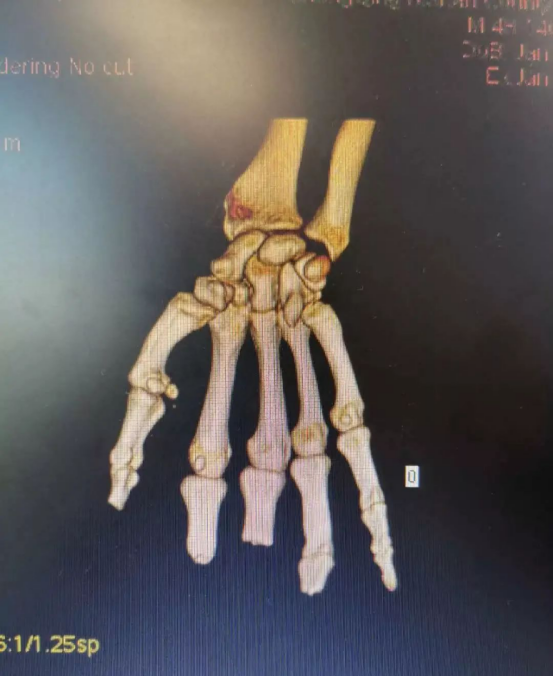

在放射科的支持下,医院对患者双手进行了CT三维重建,通过技术处理,虚拟出了患者缺失的手指,再使用新型材料打印出3D模型,模拟患者的断指。通过对3D模型进行设计取样,对患者右拇指、中指精准再造。